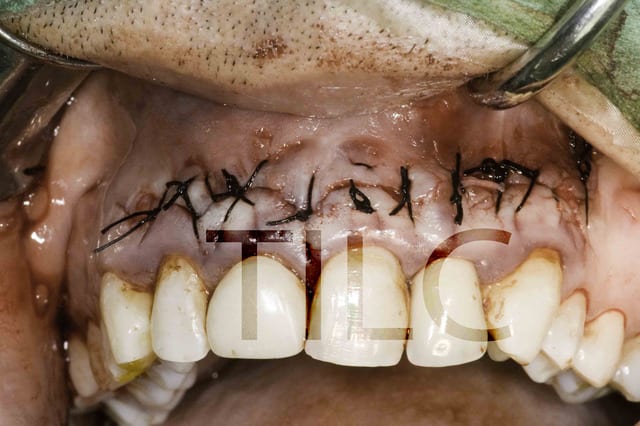

Sourire gingivale a mort, une CCM faite l'année derniere.

Morphotype epais et une bonne bande de gencive keratinisé.

Tout ce dont j'avais besoin pour changer un peu de la "routine" des resections apicales.

Mais apres analyse des photos jme suis dit que j'aurais du moins m'emballer sur la longueur !

Mais je pense que tu aurais pu aller un peu plus loin distalement. Aussi, les sutures semblent grosses et la soie n'est pas le meilleur matériel, trop de bactéries.

C'est vrai que les sutures sont degueulasses le jour de la dépose mais le titulaire est une barre de fer :)

Pour la technique c'est le lambeau d'ohsenbein lubke.

Il faut une bonne bande de gencive attaché(5mm), parodonte epais et comme ca t'évite les recession autour des jolies CCM que tu viens de faire.

Il faut bien maitriser ta technique chirurgicale pour aller vite. Tu sectionnes avec ce lambeau tout l'irrigation.

C'est pas pour de la mucco gingivale c'est pour une resection apicale simple mais n'empeche que ca fait pas propre.

Pour ferme ce genre de lambeau vous utiliser quels type de points ?

La j'ai essayé des points en X pour plaquer la muqueuse mais je suis pas super fan.